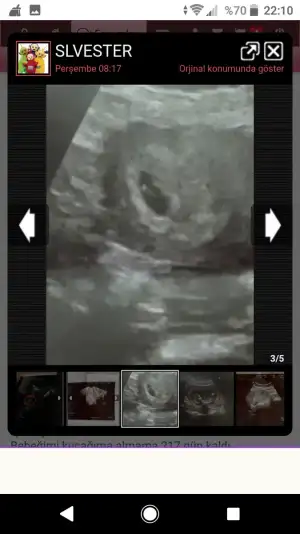

Seninki evham. Uyuyor olabilir neden uyumasin ki. Rahat ve sakin ol. Birdahaki gidişinde çikolata ye git. Hareketlenir.Kızlar bisey sorucam lutfen bilen söylesin şimdi sizin mesajlarınızı tek tek okuyunca fark ettim ben 9+6da bi kaç gun once yani doktora gittim salak bi doktordu ilkkez gittim doktor arayışımız olduğu için bebek hareket etse görür muyduk dedim görürdüm ama suan hareket etmiyo uyuyor diye. Bu dönemde bebek uyurmu yani bide uyumasi bana mi denk geldi sizce bi sıkıntı var mıdır ya kalbini dinletti kalbi atıyordu yavrumun ama neden kıpırdamıyordu(((((

benim doktorum hiçbir şey görünmüyor erkeğe biraz daha fazla benzettim dedi. yine de alışveriş yapmayın yanılma payı var dedi

benim doktorum hiçbir şey görünmüyor erkeğe biraz daha fazla benzettim dedi. yine de alışveriş yapmayın yanılma payı var dedi